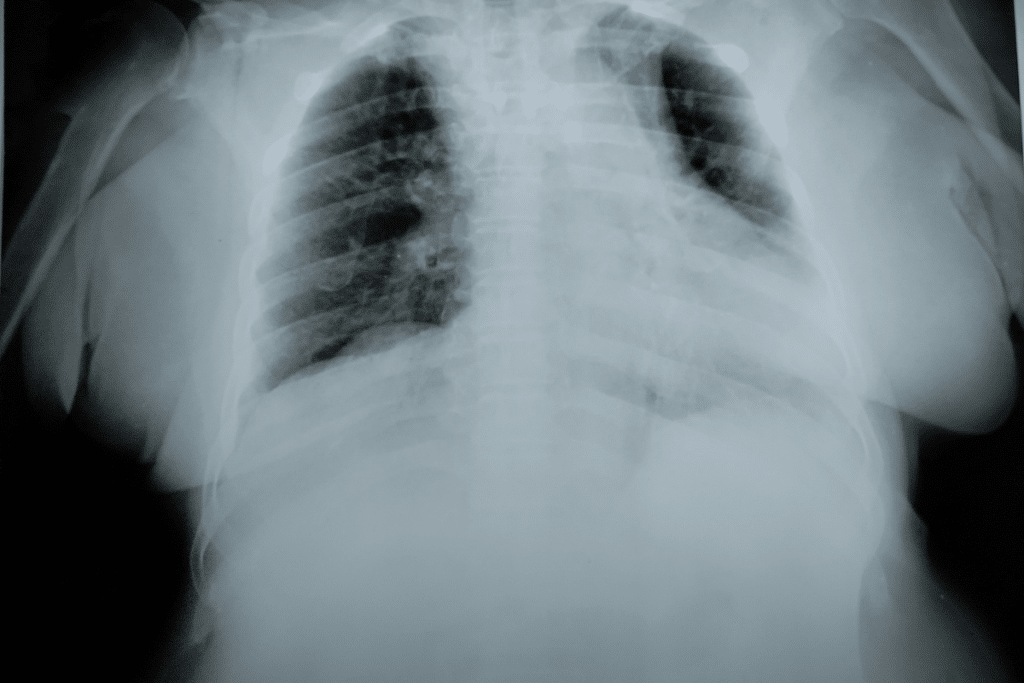

Des examens complémentaires, tels que la radiographie thoracique ou l’échocardiographie, contribuent à identifier la cause exacte de l’insuffisance respiratoire et à adapter le traitement à l’origine spécifique de l’œdème pulmonaire.

Seule une auscultation professionnelle et des examens d’imagerie permettent de distinguer l’œdème pulmonaire d’une pneumonie, d’une embolie ou d’un coup de chaleur. En général, l’œdème pulmonaire présente une accumulation visible de liquide dans les poumons lors d’une radiographie thoracique.

| Œdème pulmonaire | Ombres diffuses dans les deux champs pulmonaires |

| Pneumonie | Opacités localisées ou segmentaires |